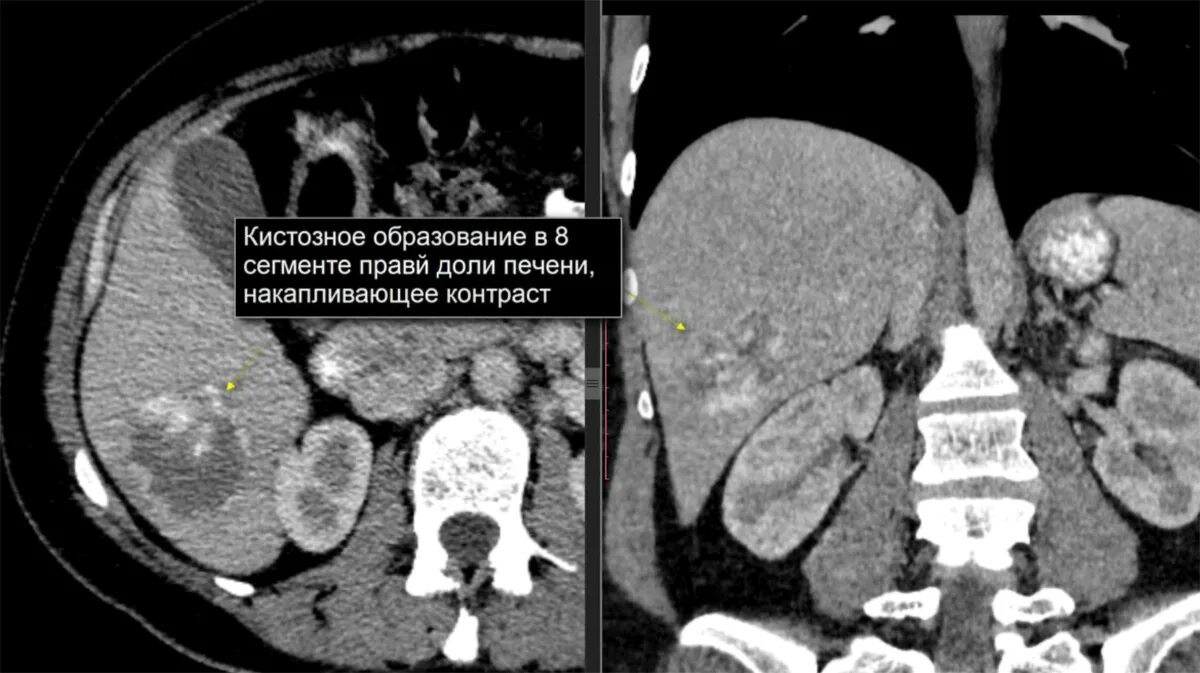

Образования печени кт